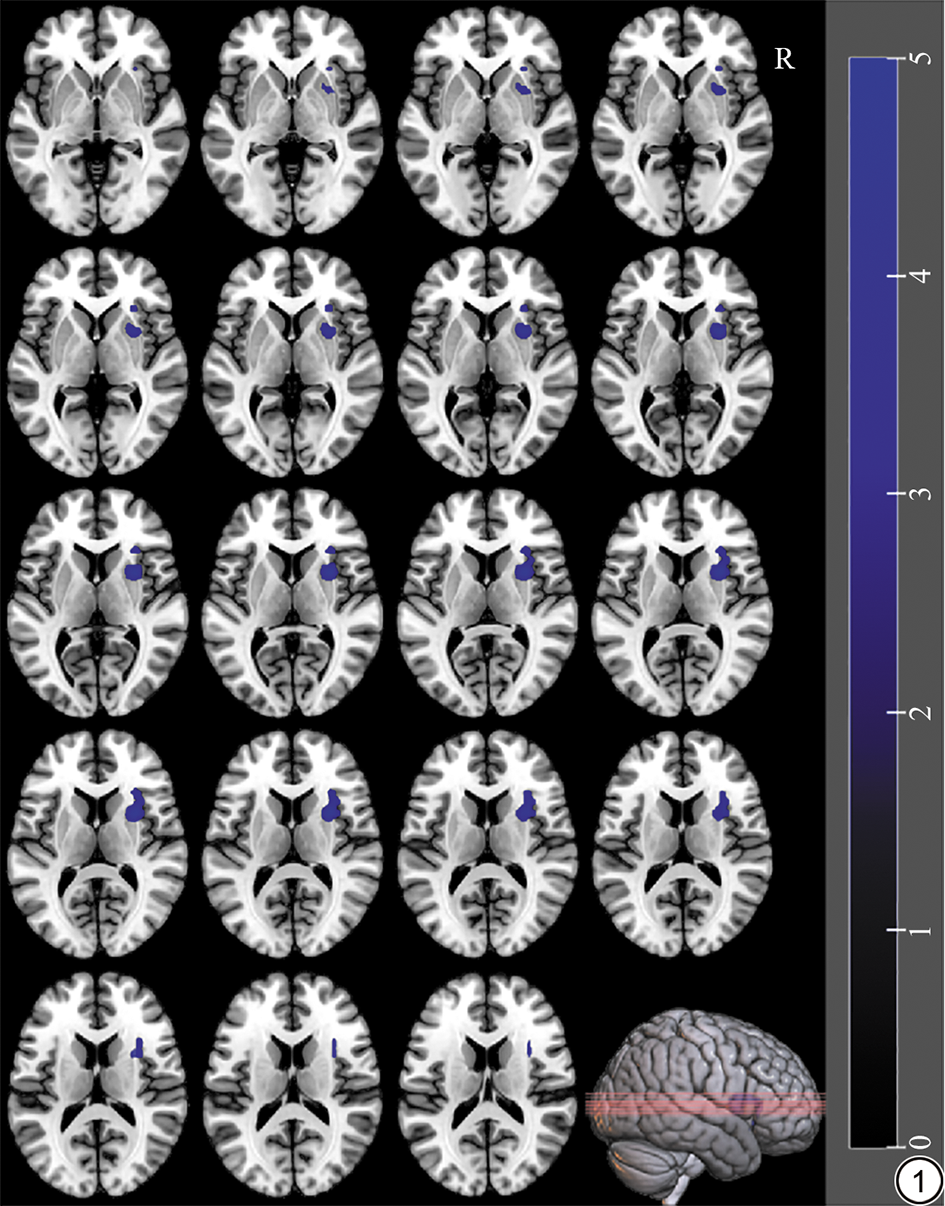

2.2 两组间CBF分析结果

基于团块水平的分析结果显示,与HC相比,MDD伴NSSI的患者的右侧壳核、右侧岛叶的CBF值下降(P<0.05,FWE校正,t=4.9)。如图1所示。

图1  健康对照者与重度抑郁症患者伴非自杀性自伤患者CBF差异脑区。CBF:脑血流量。

Fig. 1  The differences in CBF brain regions between healthy controls and patients with major depressive disorder accompanied by non-suicidal self- injury. CBF: cerebral blood flow.